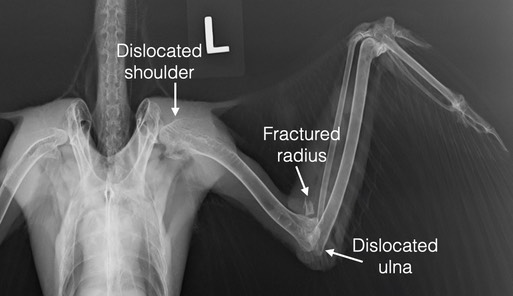

The initial exam found a very swollen left elbow and bruising from the wrist to the shoulder. There was a wound on the underside of the wing just above the elbow. A radiograph showed the radius was fractured very close to the elbow, the ulna was dislocated at the elbow and the humerus was dislocated at the shoulder. We concluded that the hawk must have collided with something at a high rate of speed. The damage to the wing was not repairable and the hawk was humanely euthanized.

When Samantha performed a necropsy it became apparent that the hawk had been shot. Once the feathers were removed from the wing, a tiny entrance wound was visible in the skin. The projectile entered the wing about one inch from the wrist, traveled through the muscle parallel to the radius and exited the wing just before reaching the elbow. The force of the projectile fractured the radius, dislocated the ulna and dislocated the humerus.